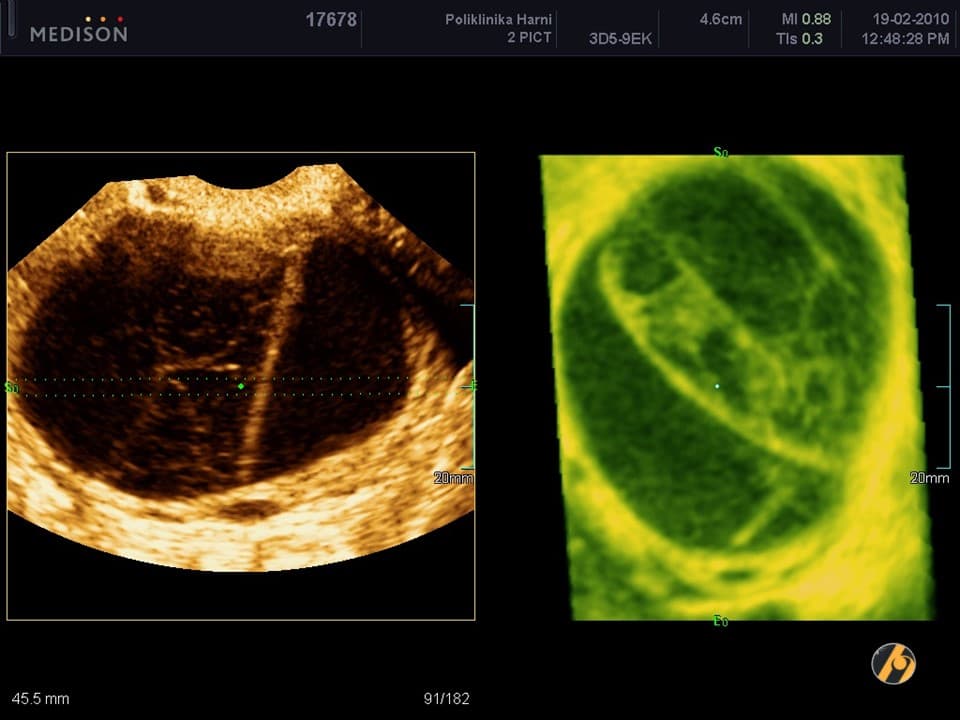

Negdje krajem 2. tjedna od početka menstruacije dolazi do pucanja folikula na jajniku, mjehurića ispunjenog tekućinom, a u kojem se nalazi jajna stanica, što se označuje pojmom ovulacija. Ovulacija je vrijeme najveće plodnosti žene. Jajnu stanicu prihvaćaju jajovodi svojim tankim tereptljikama i tijekom sljedećih 12 do 24 sata transportiraju ju u maternicu. Tijekom ovog putovanja jajne stanice kroz jajovod dolazi do oplodnje. Jajna stanica je sposobna za oplodnju svega nekih 4 sata po ovulaciji, no spermatozoidi mogu živjeti i do tjedan dana u vratu maternice te sačekati na neki način ovulaciju. Spolni odnos u vrijeme ovulacije ne označuje i sigurno nastupanje trudnoće - šansa za rođenjem djeteta iz odnosa u vrijeme ovulacije iznosi oko 35%.